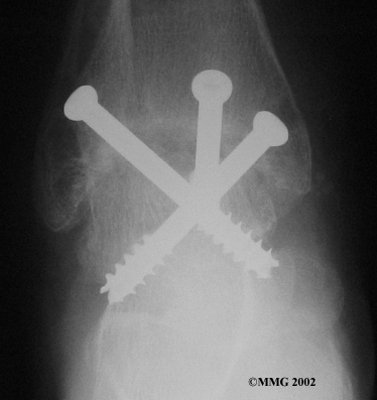

It is important when the surfaces are removed that the angles of the cut surfaces are correct. When the tibia is brought against the talus, the foot should be at a right angle to the lower leg. Once the cuts are made the bones must be held in place while they fuse. This can be done using large metal screws and metal plates if necessary. The screws are usually under the skin and are not removed unless they begin to rub and cause pain.

Inserting the screws

After ankle fusion, the physical therapists at FYZICAL San Marcos can help you learn to walk smoothly and without a limp. Although time needed for recovery varies among patients, an ankle brace will typically replace your cast after eight to 12 weeks. Your surgeon will take X-rays frequently to see if the bones are fusing together. You will probably need to use crutches during the time you wear the cast. As the fusion grows stronger, you will begin to put more weight on your foot when walking.